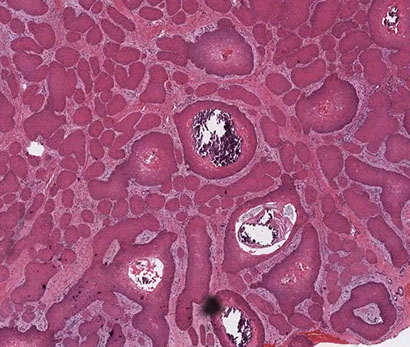

Pilomatrixoma

Trichohyaline granule (which are usually seen in hair shafts) in a pilomatrixoma

- aka calcifying epithelioma of Malherbe

solitary, bluish, firm (often calcifies), benign subepidermal spherical nodule

b9 hair follicle tumor

MC on face of kids or young adults

- 75% of childhood adnexal tumors

- can have multiple lesions in myotonic dystrophy

Sharply circumscribed cyst-like structure in dermis, possibly contiguous with hair follicle (may arise from hair matrix)

- can have inc mits (the malignant form is rare and usually very atypical)

- may have trichohyaline granules (which are usually seen in hair shafts)

3 cell types in fragmented cyst wall:

1) outer layer of blue (basophilic) basaloid martical cells with round nuclei and scant cytoplasm which dies and become dead keratin, which are the ghost cells

- imitate the cells in the root, or bulb of a normal hair follicle

2) mixed zone of eosinophilic cells c large round vesiculated nuclei

3) central zone sheets of keratinized pink "ghost" or "shadow" cells c distinct cell borders and central unstained nuclei

- difference from BCC: basaloid cells undergo abrupt keratinization and form "ghost" cells

Has foci of foreign body reaction, calcifications and ossification in shadow cell lobules

See melanin in shadow cells

Fibrotic stroma infiltrated with granulomatous inflam

Solid nests of basaloid cells may cause misdiagnosis of BCC

Ddx: Basal cell carcinoma c matrical differentiation (differs by continuity with epidermis and abrupt transition into shadow cells without the eosinophilic zone)